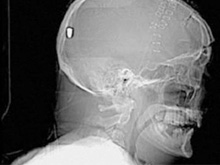

В Британии врачи нашли у пациента пулю в голове13.05.10 13:07 Прочтений новости 1144 Общество В Британии у пациента, который поступил в клинику с подозрением на инсульт, врачи обнаружили пулю в голове. Но остается неизвестным, как мужчина получил ранение.Рентгеновские снимки головы показали, что в полости черепа находится инородный предмет. Мужчине сделали томографию головы, и врачи установили, что этим предметом является пуля. Как сообщается, 19 апреля 61-летний Питер Хесфорд упал во время работы у себя в саду. Позже его обнаружила жена, которая вызвала скорую. Мужчина оставался в сознании, но не мог говорить. Медики, прибывшие на место, заподозрили у Питера Хесфорда инсульт и доставили его в Больницу Уитеншо. Эксперты по баллистике, изучив снимки пациента, пришли к выводу, что пуля, застрявшая в затылочной области, могла попасть туда через глаз. Но мужчина не помнит, что именно с ним произошло. Врачи попытались удалить пулю, однако это оказалось невозможным из-за ее положения по отношению к окружающим структурам. Пациент остается в больнице, а его состояние расценивается как стабильное. Комментарии (всего 0)